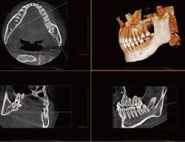

難しい親知らずの抜歯では、より精査するためにこちらからCT撮影をご提案させていただく場合があります。